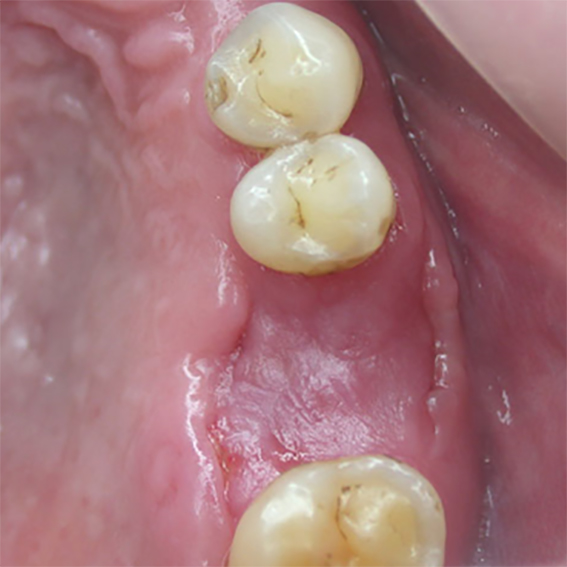

- Excellent would healing underneath

Pure titanium membrane of ultra-thin thickness of about 10 microns (0.01mm). Totally inert, biocompatible and non-biological thus removing the fear of disease transmission from collagen of bovine source. It allows ease of handling and adaptation over the operative site. Because of its mouldability, it does not require pin or screw fixation, thus avoiding the risks of pin or screw swallowing or aspiration. Excellent clinical performance in guided tissue regeneration. Resistance to infection after exposure. Primary wound closure is not necessary. No tissue reaction or wound infection.